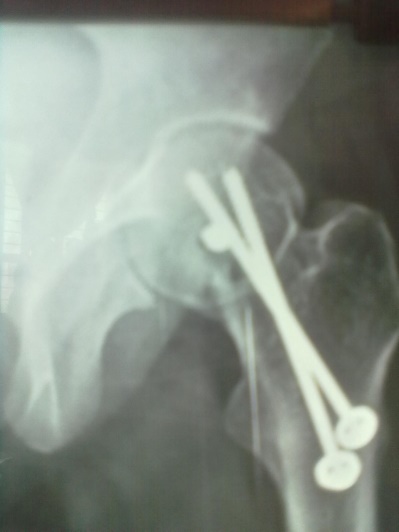

Sixteen patients of ununited fracture neck of femur (presenting late i.e. more than 3 weeks) in the children and adolescent were treated with quadratus femoris based muscle pedicle bone graft with internal fixation between 2004 to 2019. Pathological fracture, recent fracture and compound fracture were excluded from study. Mean age was 14.25 years (standard deviation 1.27 and range 12 to 16 years). Boys dominated our series (n=10 i.e. 62.50%) and right side was more commonly involved (n=12 i.e.75%). All of them were investigated for their fitness for spinal block or general anaesthesia. Steps of procedure including patient positioning, surgical procedure, provisional fixation and definitive fixation were discussed and documented. Radiographic evaluation included A-P View in 15 degree internal rotation, and Lateral view. Average delay in presentation was 5.88 weeks (range was 3-10 weeks). We had 02 transepiphyseal, 11 transcervical and 3 cervicotrochanteric fracture in our series. All the fractures were displaced and having some absorption of femoral neck.

Spinal block was used in the procedure. Prone position on fracture table with radiolucent top was used. Fracture site was exposed through posterior approach and sclerosed margins of the fragments were freshened. Fracture was reduced with appropriate neck shaft angle and fixed with Moors pin/ knowels pin or 4 mm /7mm partially threaded cancellous screws. Any rotation or tilt was corrected. The fixation was augmented with quadratus femoris muscle pedicle bone graft harvested from intertochateric crest area with a bone pedicle of length 2 cm, width 1 cm and depth 1 cm. The graft was secured to the proximal femoral head fragment with 3.5mm cortical screw or 4mm cannulated cancellous screw. Soft tissue closure was done over drain.

Patients were followed up at 2 weeks, 4 weeks, 6 weeks, 8weeksk, regularly at 6 week interval for next 6 month and then at three month interval up to two year. Radiographic analysis was performed at each follow up with special attention to extent of callus formation, alignment of fragments and hard ware integrity.